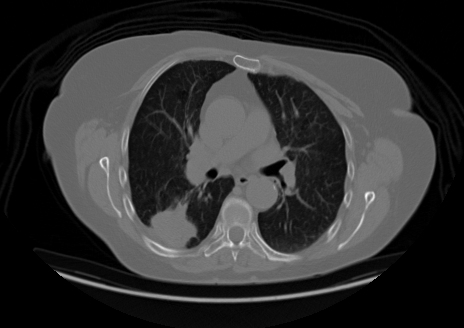

Upload your own CT slice, or click any patient below to instantly see the model classify a real scan.

Try a real scan— click any patient to run inference instantly

INPUT

OUTPUT